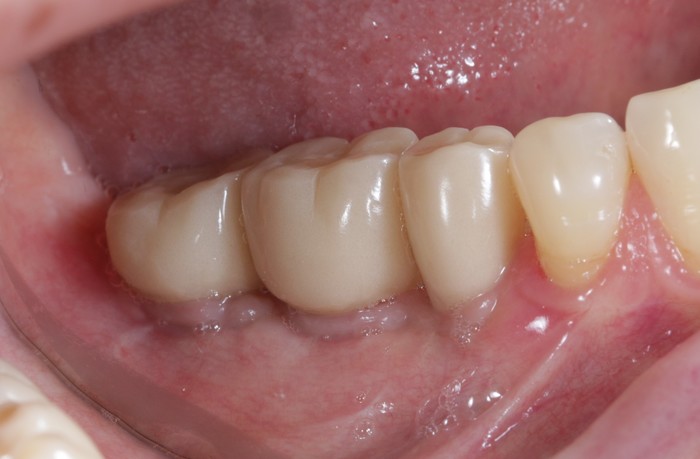

Вот пример того, когда пациент пренебрёг данным правилом:

Мужчине были установлены и спротезированы (временными коронками) имплантаты в другой клинике. После этого он пропал на несколько лет, не закончив полностью свое лечение. Явился лишь тогда, когда почувствовал «дискомфорт».

Кроме несостоятельности старых коронок и пломб, патологической стираемости зубов и т.д. - все эти годы сильно страдала гигиена.